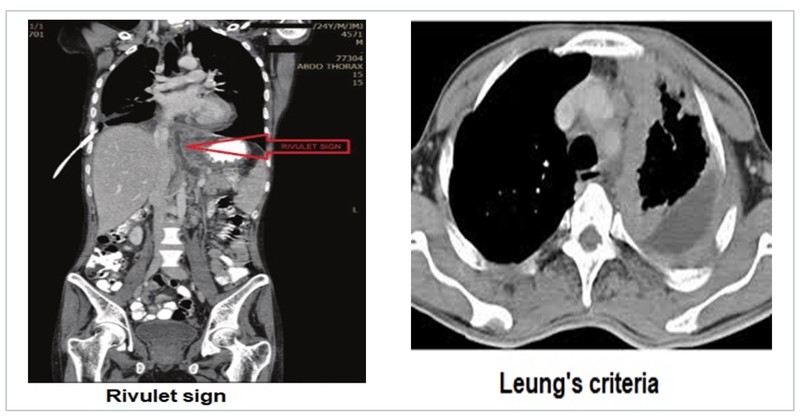

Pleural diseases are often diagnosed with the help of chest radiographs. However, CECT thorax can help further in detailing the anatomy of the pleura often giving a clue to the aetiological diagnosis. The comet tail sign results due to trapping of lung parenchyma in the two layers of pleura during resolution of a pleural effusion. The split pleura sign is a sign of empyema. A pancreatic pleural fistula is described by the rivulet sign.

Pleural plaques and there distribution may be more evident on the CT. Pleural involvement in primary or metastatic lung malignancy is observed and described as per Leung's criteria, which states that any of the following four features of pleural thickening is suggestive of malignant pleural disease:

- Circumferential pleural thickening

- Nodular pleural thickening

- Parietal pleural thickening greater than 1 cm

- Mediastinal pleural involvement